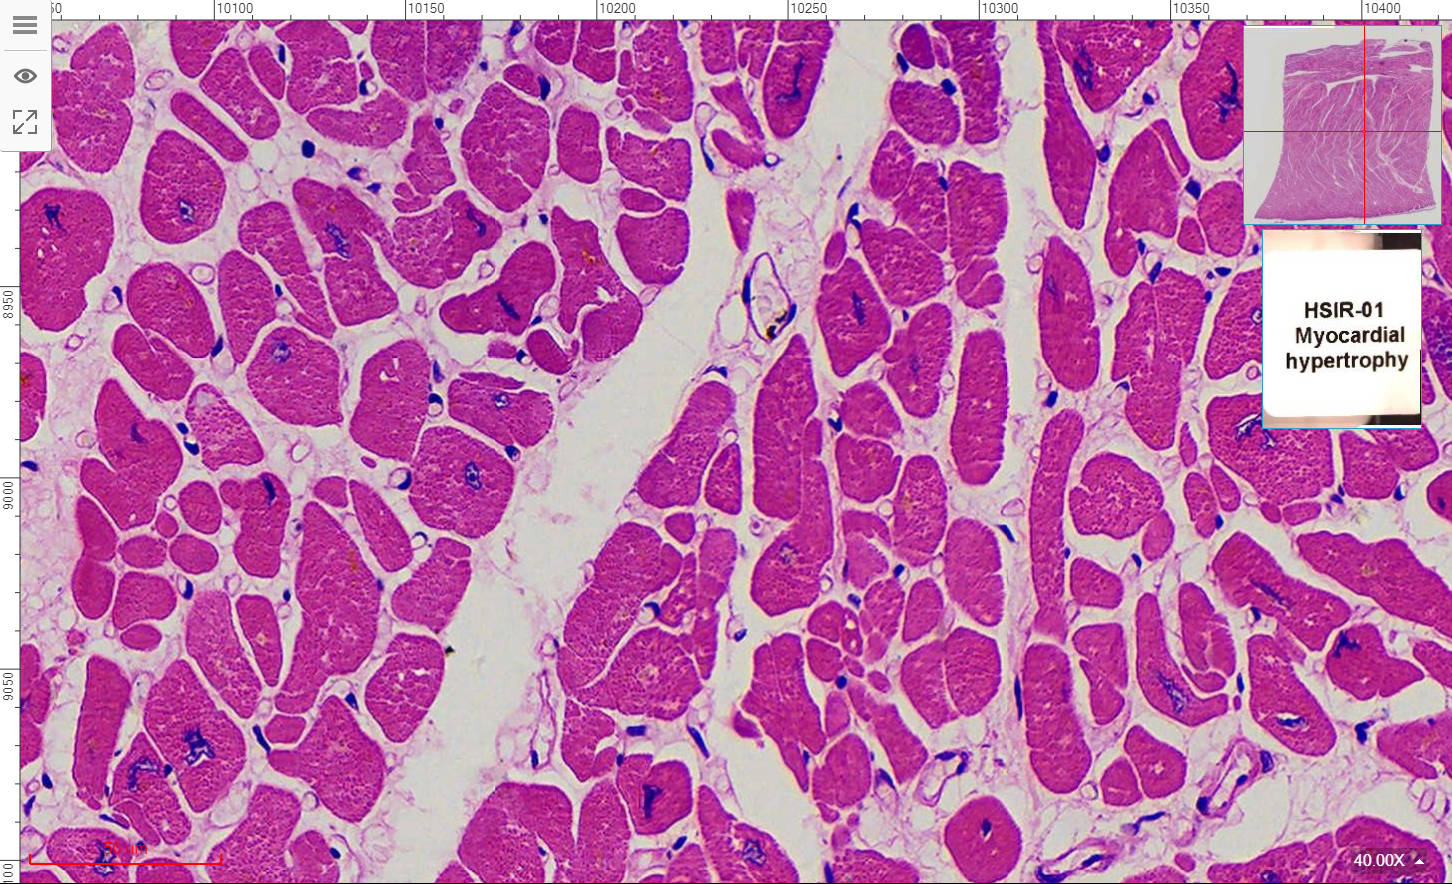

HSIR-01 Myocardial hypertrophy